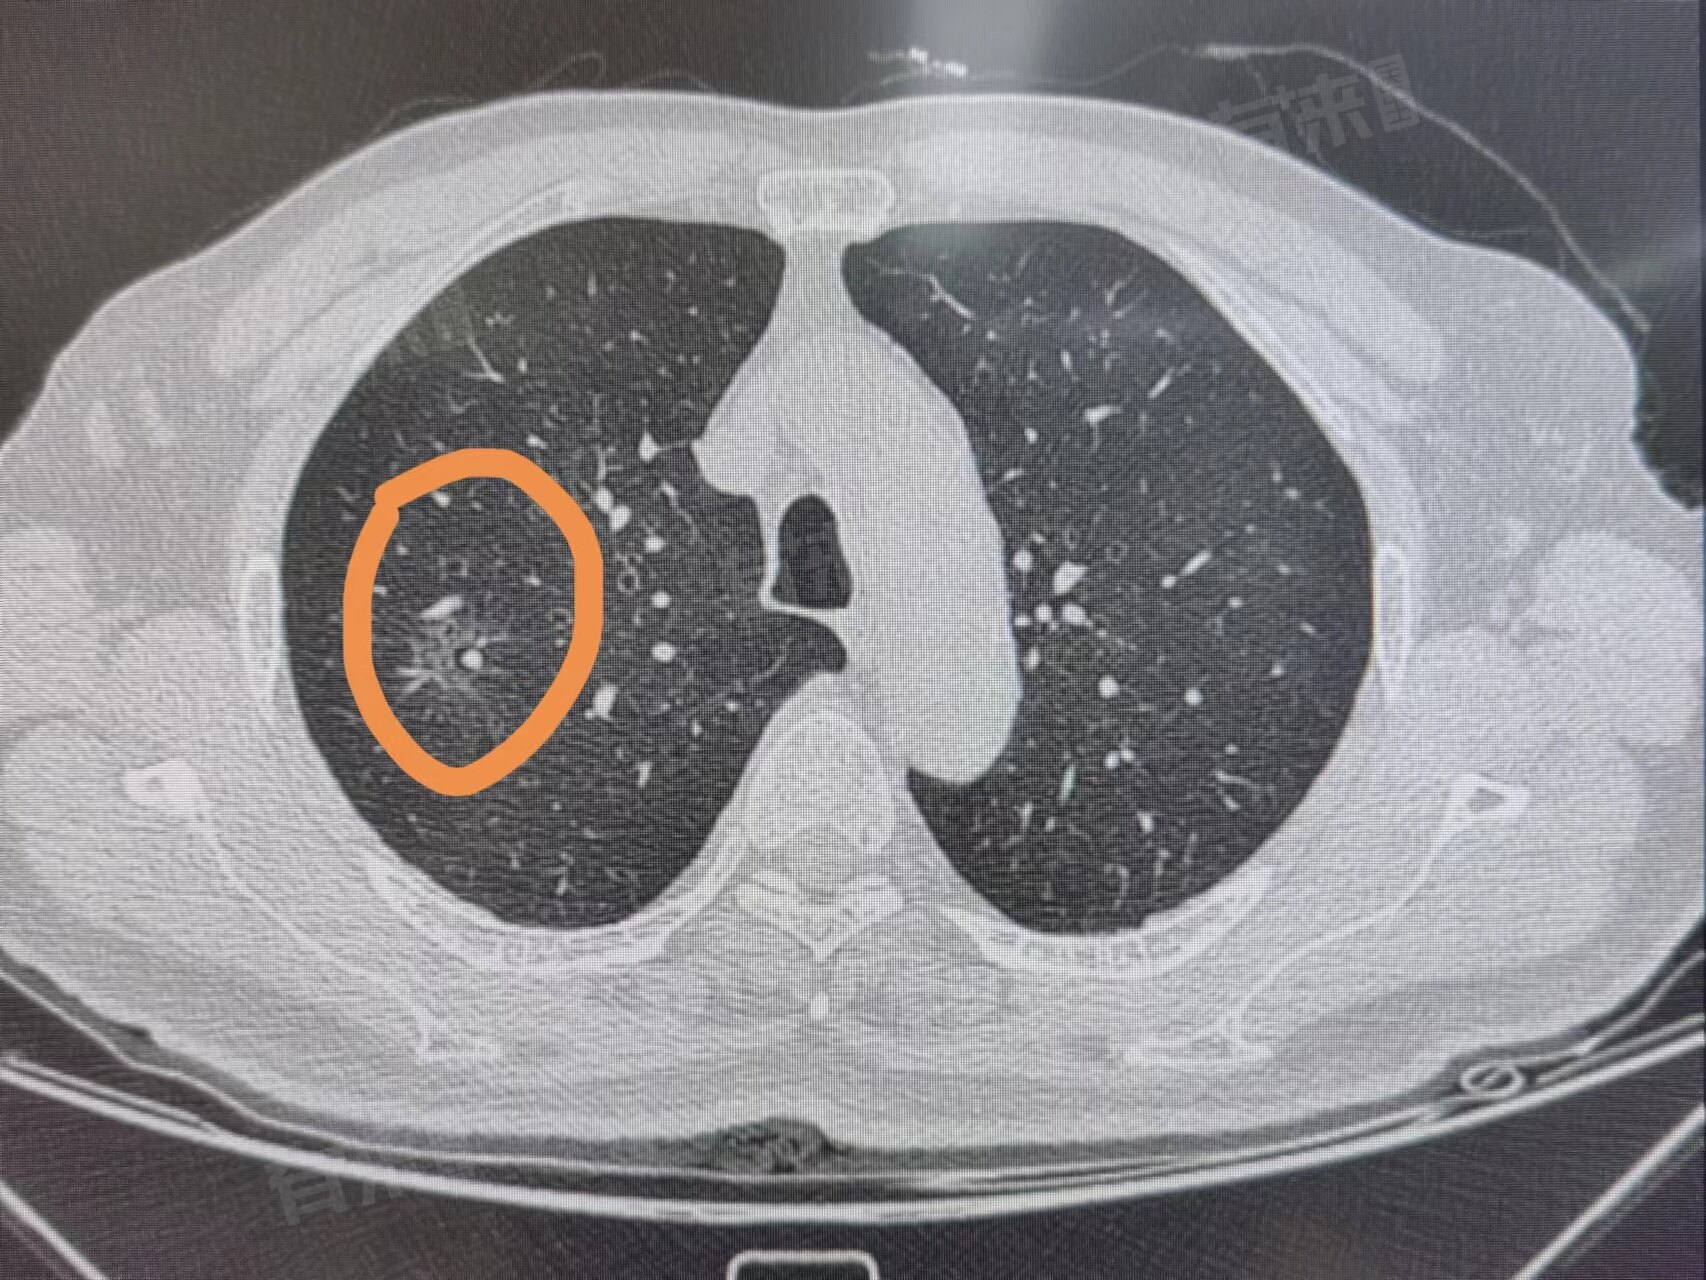

磨玻璃肺部结节有可能治好。磨玻璃肺部结节是指在肺部CT影像上表现为密度轻度增高的云雾状淡薄影,可能是良性的,也可能是恶性的早期病变,磨玻璃肺部结节的治疗效果取决于多种因素。

- 对于一些性质不确定的磨玻璃肺部结节,医生可能会建议进行密切的观察随访。在随访过程中,如果结节没有明显变化,可以继续观察;如果结节出现增大、实性成分增多等变化,则需要进一步检查和治疗。